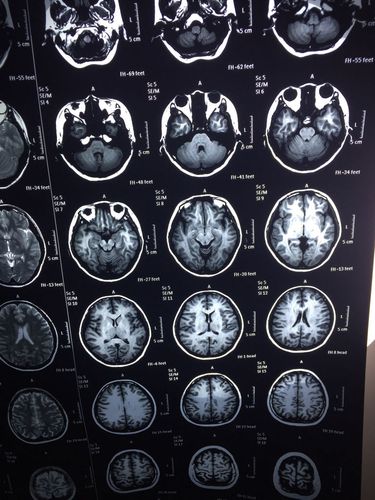

反复发作的脊髓脱髓鞘病变一例

脱髓鞘核磁共振图

脱髓鞘病变症状

脱髓鞘疾病

脱髓鞘改变

脑白质脱髓鞘改变

脑白质脱髓鞘

炎性脱髓鞘